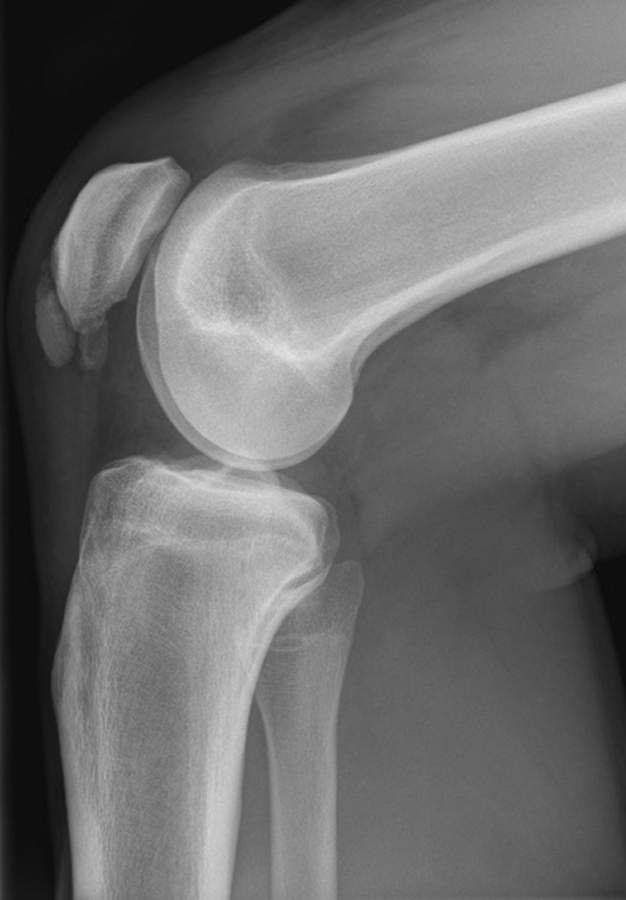

Ein Kniekiller: die Osteochondrosis dissecans. Die „Gelenkmaus“ hängt im medialen Kondylus. Ein Kniekiller: die Osteochondrosis dissecans. Die „Gelenkmaus“ hängt im medialen Kondylus. © wikimedia/nomen 49